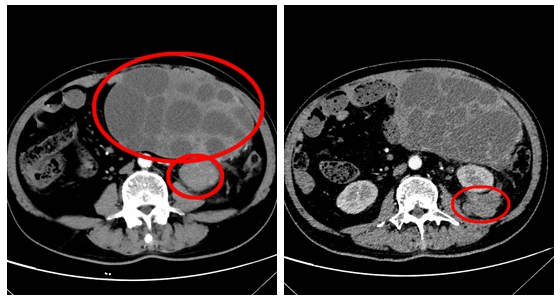

近日,湘雅常德医院普外科成功为一名61岁男性患者实施高难度腹部去分化脂肪肉瘤切除手术。本次手术的成功实施,充分体现了湘雅常德医院在复杂肿瘤诊治方面的综合实力。  ...